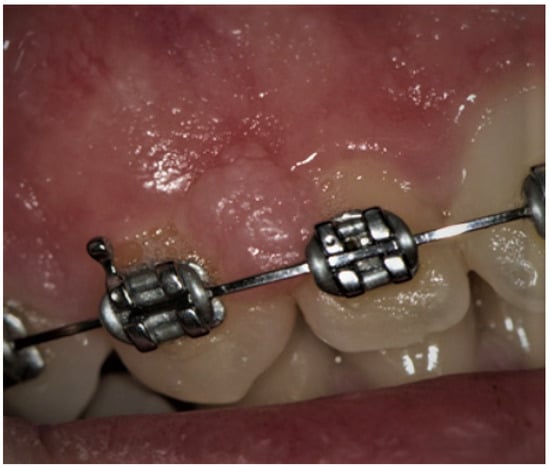

The prevalence of traumatic erosions and ulcers (Figure 11) among pediatric patients varies between studies, from as low as 1.33% up to 17.8%. This may be because the OMLs were classified differently, as certain studies included Morsicatio buccarum in this lesion category [8,9,10,15], while others, like the present study, did not [3,27,28]. In the investigations where MB was included in trauma induced mucosal lesions, its frequency was quite high, 11.8–17.8%, whereases when MB was considered as a separate pathology, the incidence of traumatic erosions and ulcers decreased to the level of 1.33% to 8.53%. In our opinion, it is more accurate to separate these two mucosal pathologies due to their different etiology, characteristics, and method of treatment. In our investigation, the prevalence of traumatic erosions and ulcers was equal in age groups, which confirmed the outcomes of the previous studies [15,27]. While other researchers did not find a gender predilection of this OML, we found a strong and significant correlation between traumatic erosions and ulcers and the male gender (p = 0.03) [8,27].

Figure 11.

Traumatic ulcer on the left buccal mucosa in a school-age boy. Visible in the picture yellow-gray, oval, well-circumscribed ulceration with rolled border. In this case, the lesion resulted from a parafunctional chewing of the cheek due to school stress.